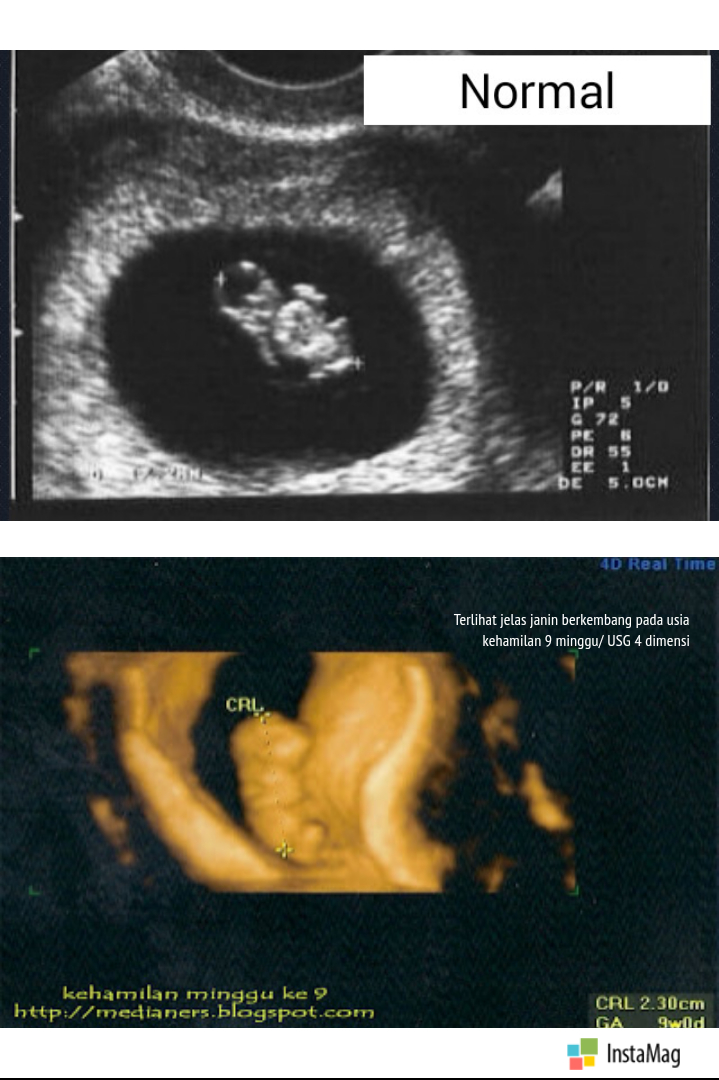

Gambar Usg Kehamilan 9 Minggu

USG 9 Minggu - YouTube Hamil 2 Bulan: Dari Embrio Menjadi Janin - Alodokter USG Kehamilan 9 Minggu | Alhamdulilah Sehat | Ita Rosida - YouTube Kenali Cara Membaca Hasil USG Untuk Tahu Kondisi Bayi - Ibupedia Cara Membaca Hasil USG yang Benar, Wajib Tahu! 9 minggu alhmdulillah detak jantung udh kedengern,, - IbuHamil.com Ketahui Tumbuh-Kembang Anak Selama Kehamilan - Kompasiana.com Manfaat USG untuk Ibu Hamil dan Janin - Ibupedia Perkembangan Janin di Minggu ke-9 Sampai ke-12 Kehamilan USG bayi 2 dimensi usia 9 minggu - YouTube Ternyata Cukup 3 Kali Melakukan USG Selama Kehamilan, Ini Penjelasannya, Moms! Nanda Novita Hertanti :.: June 2013 Netizen Peringatkan Shandy Aulia Karena USG Tiap Minggu, Bahayakah? hamil 9 minggu . Perkembangan Kehamilan Usia 9 Minggu - Mamapapa.id % USG Kehamilan, Penting gak sih ? | Ikhsan Kurniawan BILIK SONOGRAFER : Kehamilan Awal (Kehamilan Trimester 1) JANIN BELUM TERLIHAT SAAT USG? JANGAN KHAWATIR, MOMS! - susistory USG usia 9 minggu ny Lilis “RS.Hermina Galaxy” - YouTube bentuk USG janin 9w - IbuHamil.com Hamil Kosong Atau Blighted Ovum (BO) – . Perkembangan Janin Usia 9 Minggu - Bidanku.com Setelah USG Dokter Memvonis Kehamilan Kosong, Ini Sebabnya - Tribun Jambi Penantian 9 Tahun Berbuah Manis, Rianti Cartwright Akhirnya Hamil Anak Pertama - Semua Halaman - Grid.ID USG 4D Diusia Kehamilan 38 Minggu | Laci Ajaib Blighted Ovum, Kehamilan Tanpa Janin - Medianers Berapa Kali USG Saat Hamil Harus Dilakukan? Diary Kehamilan: Cerita Kehamilan Pertama, Pertama Tahu Hamil – ranselriri Ibu Hamil, Ini 12 Tandanya Bayi di Dalam Kandunganmu Sehat | BukaReview USG 9 Minggu 5 Hari - YouTube Hasil USG Umur Janin 9 Minggu | Our family home’s Blog Kapan Denyut Jantung Janin Bisa Terdeteksi? | HonestDocs 10 Tanda Tanda Hamil Kosong - Penyebab, Perawatan dan Pencegahan - Hamil .co.id USG Janin 9 minggu (Perkembangan Awal Kehamilan ) brg dr. Dian Indah Purnama di RS Bunda Margonda - YouTube Blighted Ovum, Kehamilan Tanpa Janin - Medianers Cara Membaca Hasil USG yang Benar, Wajib Tahu! Gambaran Hasil Usg Kehamilan 5 Minggu Yang Perlu Diperhatikan - Hamil.co.id Bagaimana Cara Membaca Hasil USG? • Hello Sehat Syahnaz Sadiqah Hamil 8 Minggu, Hasil USG Tunjukkan Dua Janin Sekaligus - Tribun Pontianak Ketahui Tumbuh-Kembang Anak Selama Kehamilan - Kompasiana.com Thanks, God! It’s sooooo amazing… | Selamat Datang di Istana Putri !!! USG 4 Dimensi Tidak Diperlukan Ibu Hamil? - Health Liputan6.com Perkembangan Janin Usia 9 Minggu Perkembangan janin 9 minggu - Panduan untuk ibu hamil | theAsianparent Indonesia My Pregnancy Journey - trimiyati yuliana USG untuk Pemeriksaan Kehamilan 2 Bulan ~ DOKTER OZ INDONESIA 26 Februari 2017 - YouTube Kesalahan Memprediksi Jenis Kelamin Saat Awal Kehamilan - kumparan.com USG dasar dalam kehamilan Kapan Ibu Hamil Mulai Merasakan Gerakan Janin? - kumparan.com Perkembangan janin 9 minggu - Panduan untuk ibu hamil | theAsianparent Indonesia Memasuki Hamil 9 Minggu, Apa Saja yang Terjadi? Viral, Rekaman USG Bayi Kembar Bertengkar dalam Rahim - Citizen6 Liputan6.com Memahami Air Ketuban dan Fungsinya - Alodokter Pertambahan Berat Janin Normal di Tiap Trimester Kehamilan FOTO: Hamil 10 Minggu, Rinni Wulandari Pamer Hasil USG : Okezone Celebrity Pengalaman Umrah Saat Hamil 9 Minggu - A Cup of Coffee SYOK! Dokter Kandungan Ini Kaget Lihat Hasil USG Ibu Hamil, Mencengangkan! - Halaman all - Tribun Manado Cara Membaca Foto USG: 8 Langkah (dengan Gambar) - wikiHow Dokter ketiga dalam kehamilan 9 minggu - IbuHamil.com Kapan Kehamilan Kembar Terdeteksi USG 4 Dimensi di Bandar Lampung - Info Bandar Lampung Ciri-ciri Hamil dengan Kondisi Janin Tidak Berkembang - kumparan.com Retno A Twitter: “@falla_adinda teh ini USG usia 9 minggu. Itu kepalanya kok udh dbawah ya kayakny? Eh iya gak sih? Belum USG lg soalny http://t.co/o6l2Jw7lsK” Cara Membaca Foto USG: 8 Langkah (dengan Gambar) - wikiHow Pengalaman Hamil Kembar - The Urban Mama Bumil Wajib Tahu, Inilah Penyebab Bayi Sungsang dan Cara Mengatasinya Sedang hamil, ini 10 foto USG yang kerap dipamerkan Shandy Aulia CeRiTa cHa: Para Ibu Hamil, Ini Keluhan yang Biasanya Muncul Saat Tri Semester Pertama Kehamilan Kehamilan 9 Minggu Janin 7 Minggu Jumlah Bayi Kembar yang Lahir Tak Sesuai Hasil USG? Ini Penjelasan Dokter 5 Langkah Membaca Hasil USG yang Bisa Bunda Pelajari Evan Reisha - Kontrol Kandungan Ke-6 (Trimester 2-3, 27W6D) Inilah Alasan Ibu Hamil Perlu Melakukan USG Kehamilan Perkembangan Janin 3 bulan / 12 minggu USG - Cerita kehamilanku part 3 - YouTube MND Clinic Instagram posts - Gramho.com usg hamil 9 minggu Rachel Maryam Hamil Anak Kedua di Usia 40 | Merdeka.com | LINE TODAY Sedang hamil, ini 10 foto USG yang kerap dipamerkan Shandy Aulia Mulai Rasakan Mual, Ini 6 Momen Zaskia Sungkar Cek USG Janin Pertama Kali Ternyata Positif Sedang Hamil Kembar-Keluarga si Kembar Ternyata Seperti Ini Berat Janin 3 Minggu di Awal Kehamilan dan Perkembangan yang Dialaminya - Semua Halaman - Nakita USG dasar dalam kehamilan Informasi Lengkap Perkembangan Janin dan Ibu Hamil Minggu ke-9 "Down Syndrome" Terdeteksi Lewat USG 3 Kemungkinan Penyebab Janin Tidak Terlihat di USG Diari Kehamilan Pertama: Kontrol Kandungan Ke-2 (Trimester 1, 7W6D) 10 Manfaat USG Kehamilan Bagi Janin - Hamil.co.id Hasil USG | Febriyan Indriana 31w3d pregnancy… - The Daily Rella Janin Usia Kandungan 12 Minggu Hamil USG 9 Minggu 5 hari. Deg2an janinnya berkembang atau tidak - YouTube Banyak Fungsi, Tak Hanya untuk Cek Jenis Kelamin Mengenal Peranan USG Dalam Kehamilan Selamat! Rachel Maryam Tengah Mengandung 12 Minggu, Bahagia Bagikan Perkembangan Janin - Tribunnewsmaker.com Diary Kehamilan: USG 4D Murah Meriah – ranselriri Mengetahui Usia Kehamilan Dengan USG – . Mengenal Kehamilan Kosong atau Blighted Ovum (BO) - Bidanku.com 3 Cara Membaca Hasil USG yang Benar, Biar Nggak Salah Kaprah | merdeka.com Atiqah Hasiholan Hamil 7 Bulan, Rio Dewanto Berbagi Hasil USG - Kapanlagi.com Ini Waktu Yang Ideal Untuk Melakukan USG 4 Dimensi Saat Hamil - Semua Halaman - Nakita Hasil USG Kehamilan 24 Minggu : “Istriku Hamil Mobil Sport!” | theAsianparent Indonesia